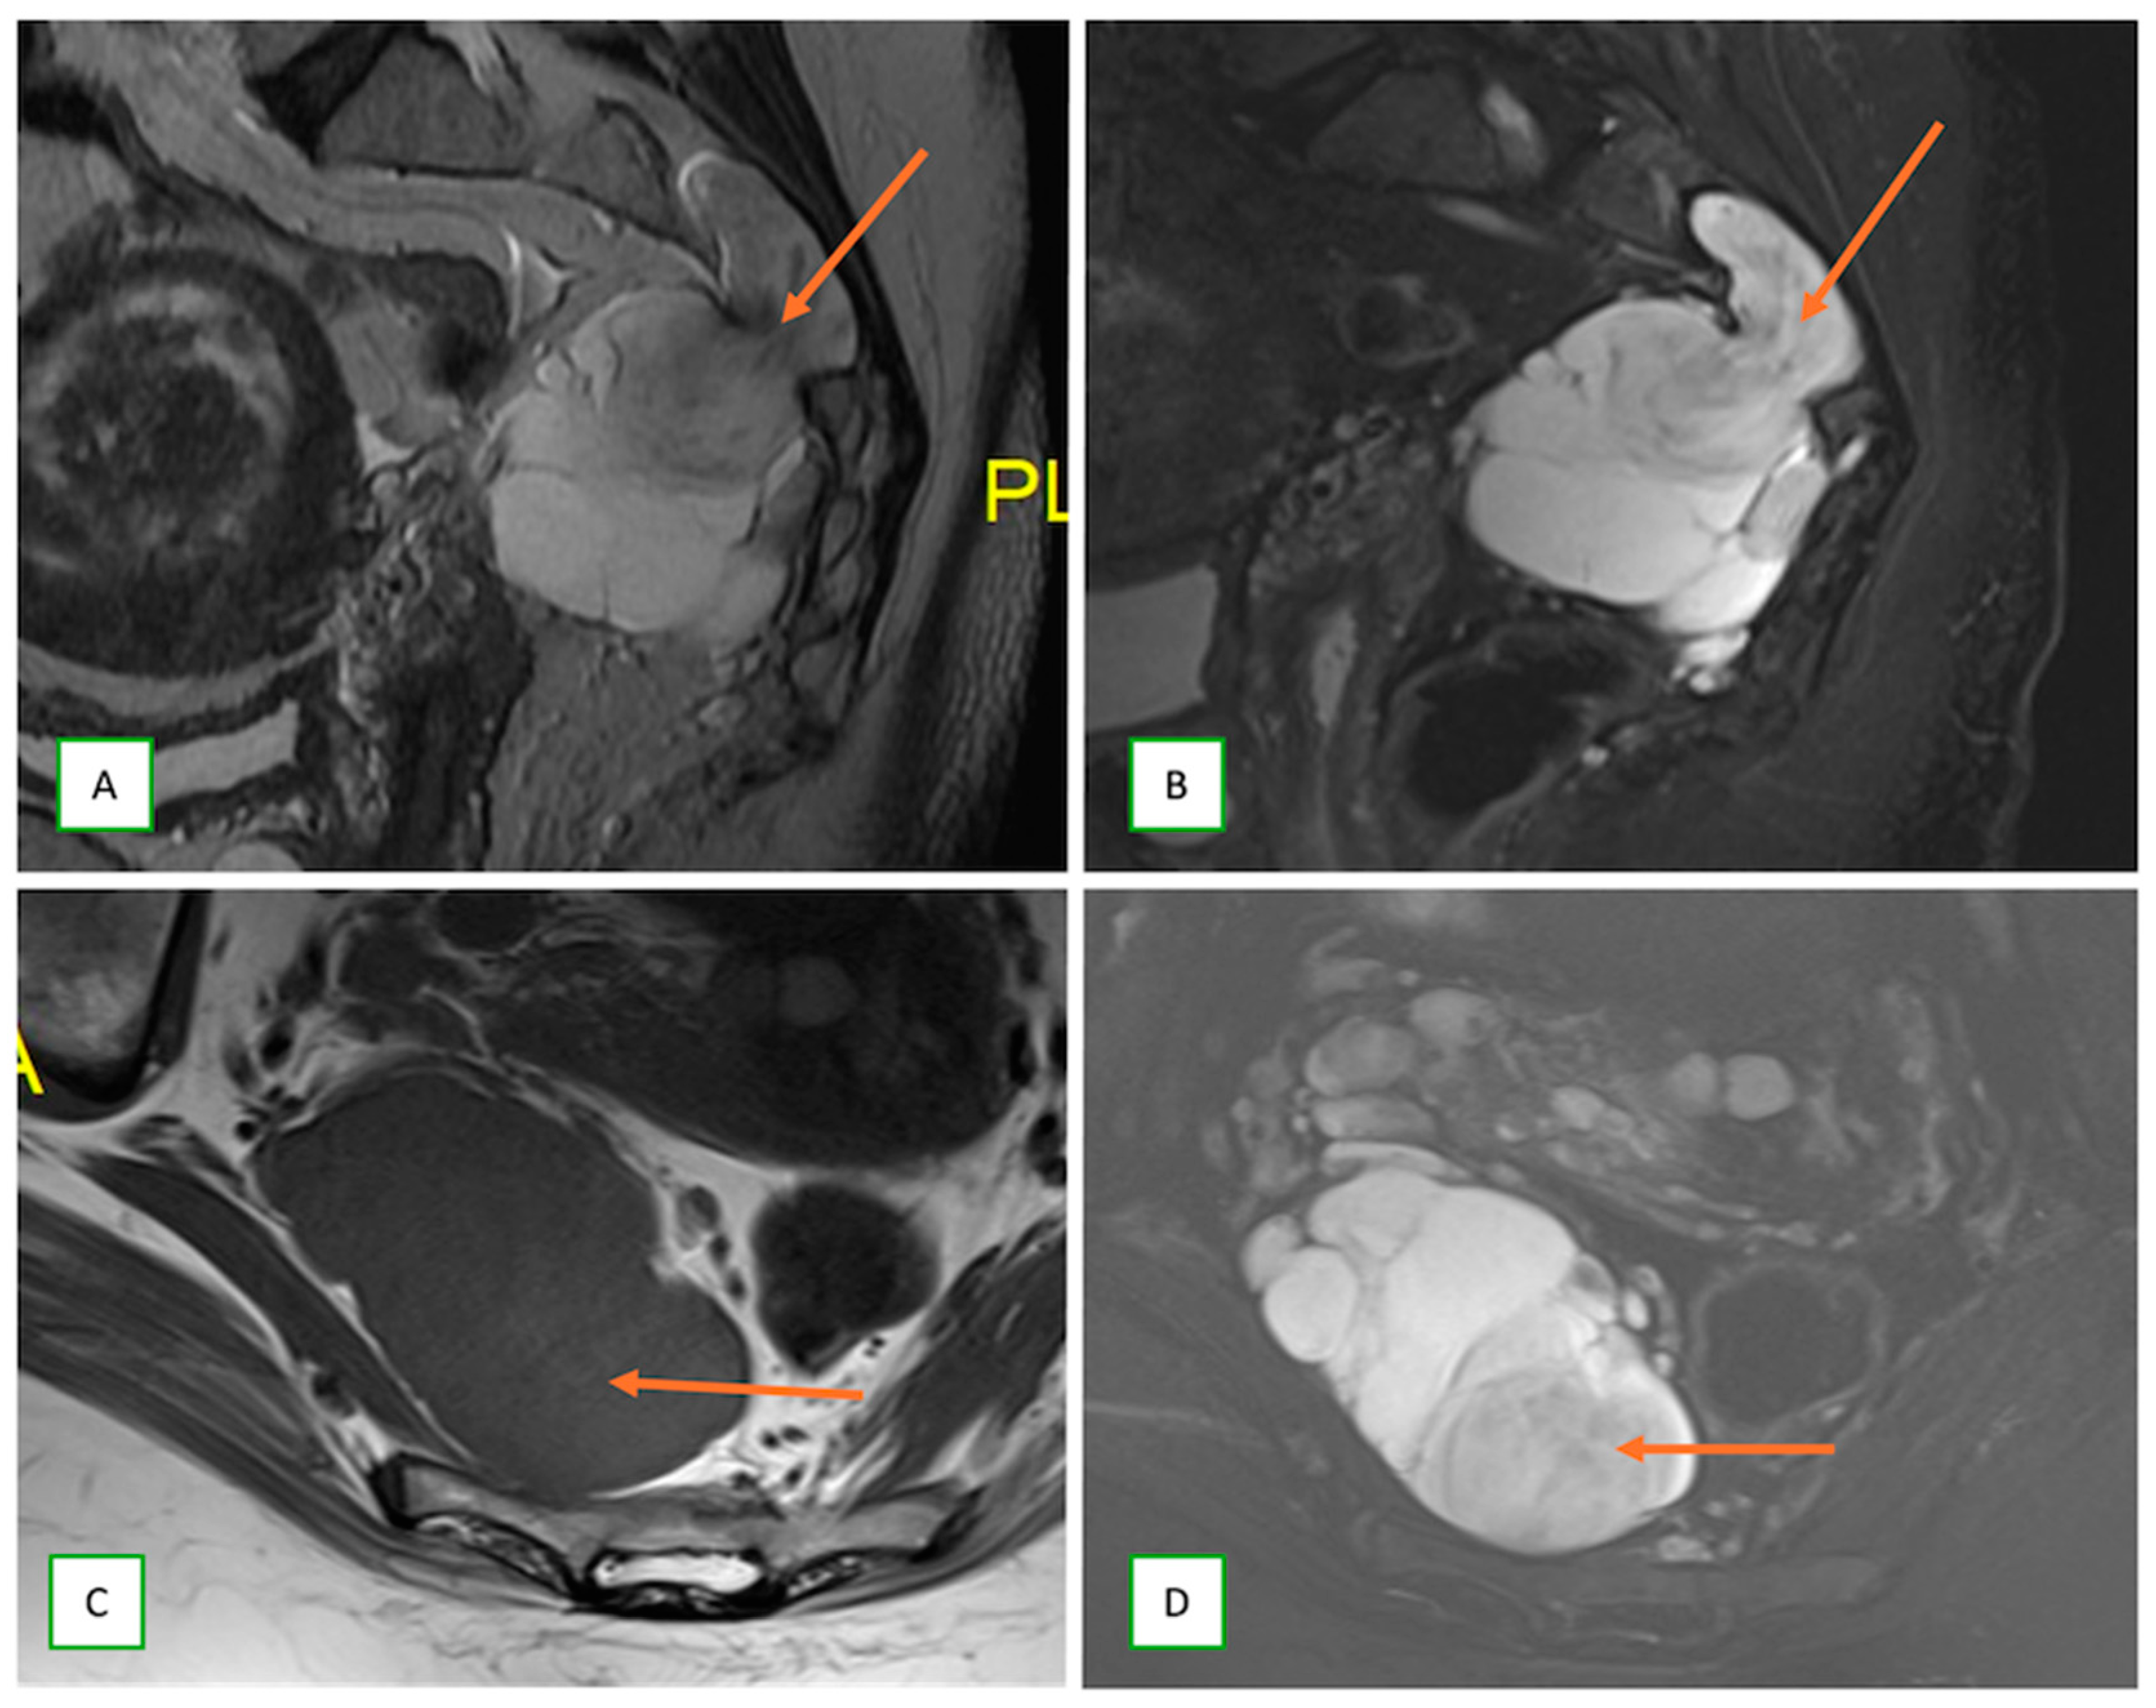

- Intraneural ganglion cysts usually occur near joints; are particularly common in the common peroneal nerve at the knee, owing to the intraarticular branch of the proximal tibiofibular joint; and appear as tubular, multiloculated cystic lesions following the course of the nerve on MRI [60,61] (Figure 16).